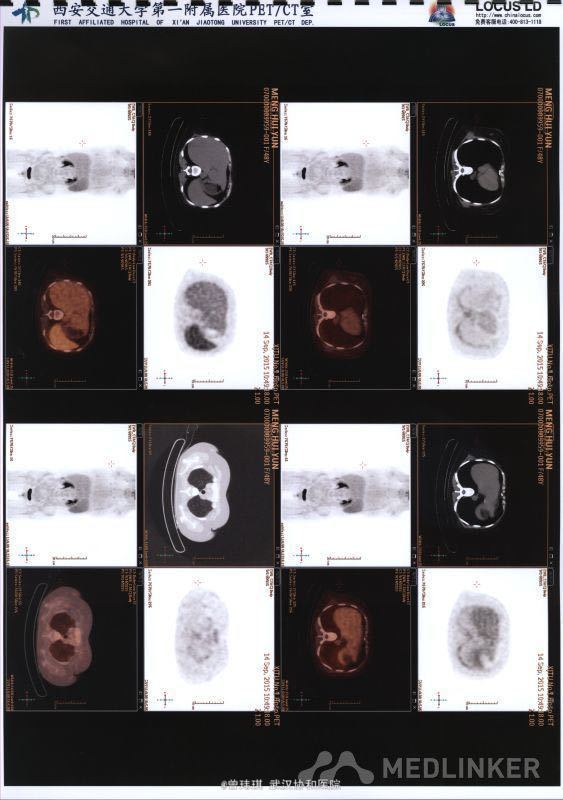

入院查体:四肢肌肉、胸骨、椎骨、膝关节压痛。双上肢肌力Ⅳ级、左下肢肌力Ⅱ级、右下肢肌力Ⅲ级;胸2平面以下痛觉减退,双侧肱二头肌、肱三头肌腱反射(++)、膝腱及跟腱反射(+-++)、左侧霍夫曼征阳性、双侧巴彬斯基征阳性。 骨髓穿刺(第一次):骨髓增生稍低,出现浆细胞卫星现象,并有瘤样改变,嗜血细胞增多,骨髓小粒中造血细胞增多。 复查骨髓穿刺(第二次):增生细胞稍低,浆细胞有瘤样改变,网状细胞、异常吞噬细胞明显。 再次复查骨髓(第三次):增生性骨髓,巨核细胞数正常,血小板减少,粒红可见轻度病态造血现象,浆细胞、网状细胞易见。 外院:血清Kappa轻链4.95g/L;免疫球蛋白G1870mg/L(723-1685),免疫球蛋白A 410mg/dl(69-382),免疫球蛋白M 31mg/dl(63-277),KAP 545mg/ml(170-370),LAM 273mg/dl。 肿瘤标志物:NSE 53.88ng/ml,铁蛋白 2476ng/ml。 自身抗体谱、血T-SPOT、G试验、GM试验、肝炎系列、梅毒、艾滋抗体等均未见异常。 PET提示右侧下鼻甲葡萄糖代谢增高,骨髓及脾脏大、葡萄糖代谢增高。 头颅MRI+颈椎+胸椎MRI扫描:1、右侧侧脑室、豆状核及外囊异常信号影,考虑脑梗塞,建议DWI检查;2、颈椎间盘突出(颈4-5、5-6,中央型);颈6椎体骨岛;3、胸3-6椎体水平椎管内异常信号影,建议增强扫描。